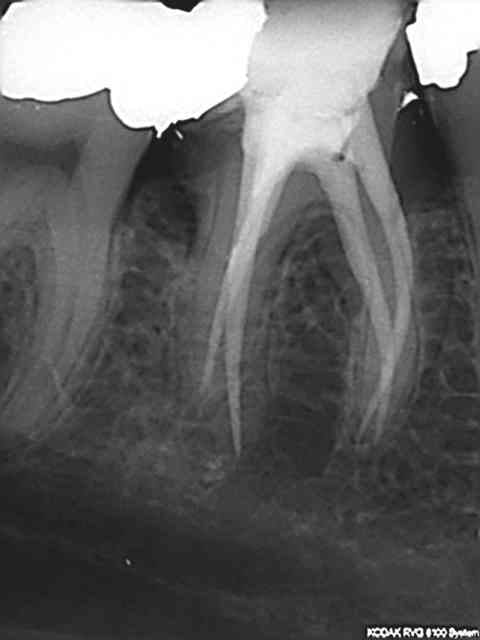

Juste pour prouver qu'on peut tout faire avec Mc Spadden, le derviche écossais:

Canal large, on est allé au F5 sans toucher les bords, cône calibré à 55 à l'apex, thermocompacteur à 3mm de la LT. Pas d'anesthésie.

21 ckpvf9 - Eugenol